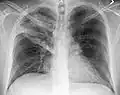

Normal AP CXR

-

Normal lateral CXR -

AP CXR showing left lower lobe pneumonia associated with a small left sided pleural effusion -

AP CXR showing right lower lobe pneumonia -

AP CXR showing pneumonia of the lingula of the left lung -

Right upper lobe pneumonia as marked by the circle. -

Left upper lobe pneumonia with a small pleural effusion.

Right lower lobe pneumonia as seen on a lateral CXR